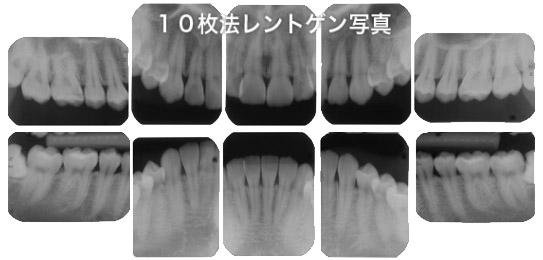

10枚法デンタルレントゲン写真